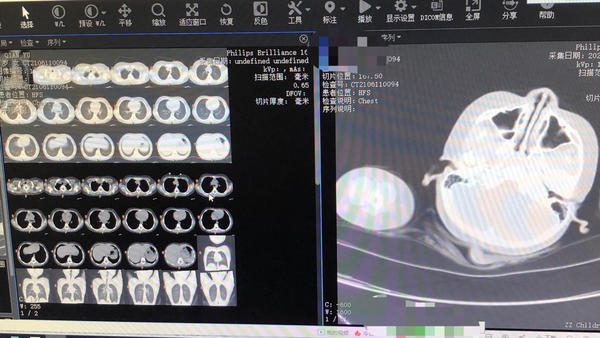

在河南省儿童医院南院区就诊,彤彤被确诊为“吸入性肺炎”,这可把家长急坏了,赶紧给彤彤办理了住院手续。

河南省儿童医院南院区普内科一病区主任宋春兰还记得当时彤彤的状态,精神反应十分不好,呼吸困难明显,口唇发绀,吸气时右侧胸痛。立即入抢救室给予鼻氧管吸氧、心电监护、抗炎等对症治疗。